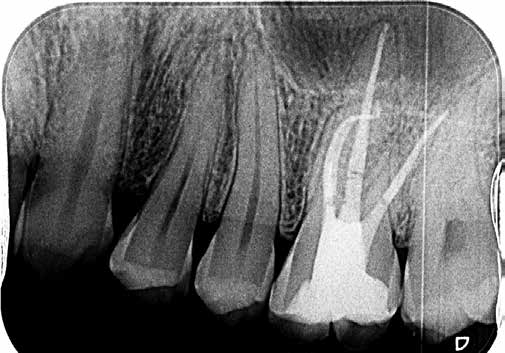

Bei der Diagnose des schmerzfreien Patienten stellte sich die beschriebene Erhebung schließlich als Fistel heraus (Abb. 1). Der Zahn 26 sowie die Nachbarzähne wurden zunächst einer Sensibilitätsprüfung unterzogen, wobei der Kältetest an Zahn 26 negativ ausfiel. Im Anschluss erfolgte dann die Anfertigung der diagnostischen Röntgenaufnahmen (Abb. 2 und 3). Dazu wurde ein Guttapercha-Stift in den Fistelgang eingebracht, um die Lokalisation der Entzündung zu erleichtern. Speziell bei der distal exzentrischen Aufnahme ließ sich dabei an 2 Wurzelspitzen des Zahns 26 die Entzündung ausmachen (Abb. 2). Insofern war in diesem Fall eine endodontische Behandlung des Zahnes angezeigt. Für diese wurde sogleich ein Folgetermin vereinbart.